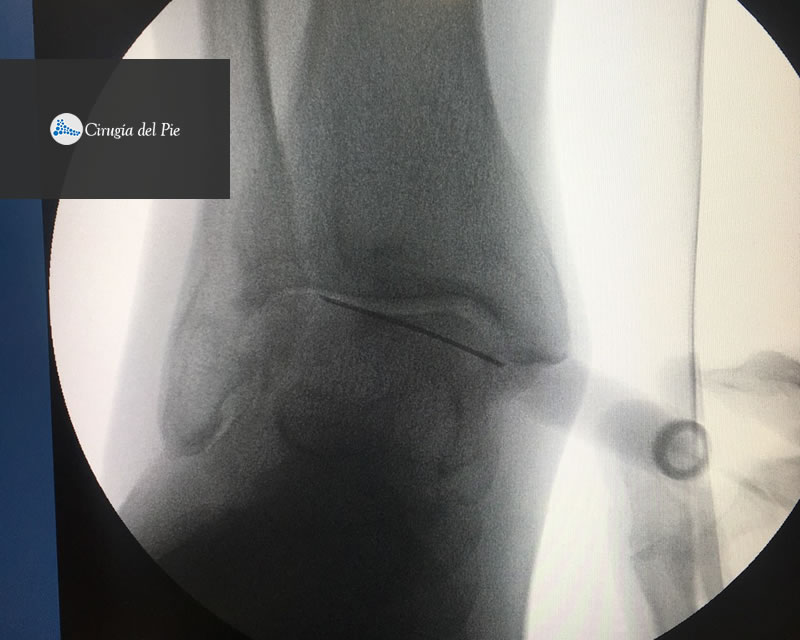

Se obtiene de la sangre del propio paciente. La muestra es procesada en forma específica en una centrífuga, separando las distintas fracciones de la sangre. Una de ellas, es el plasma con concentrado de plaquetas. La característica principal de esta fracción es que presenta una gran cantidad de factores de crecimiento que promueven la migración y diferenciación celular para la reparación de los tejidos. Este material puede procesarse para ser utilizado en forma líquida o gelatinosa, pudiendo ser aplicado en tratamientos de cura avanzada de heridas y úlceras, también a nivel muscular, tendinoso, ligamentario y fracturas, como así también en forma intraarticular. Habitualmente lo hacemos en forma ambulatoria.

Plasma rico en plaquetas Dr Masaragian